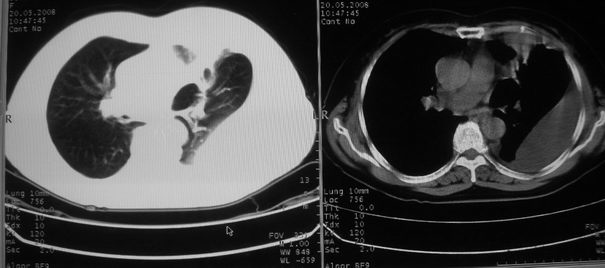

以下是引用w_jianhua在2008-5-22 12:59:00的发言:[br]1.左肺上叶肺癌并左侧胸腔积液可能性大。2不除外支气管内膜结核并包裹性胸腔积液,建议支气管镜检3.左肺下叶肺大泡,肺气肿